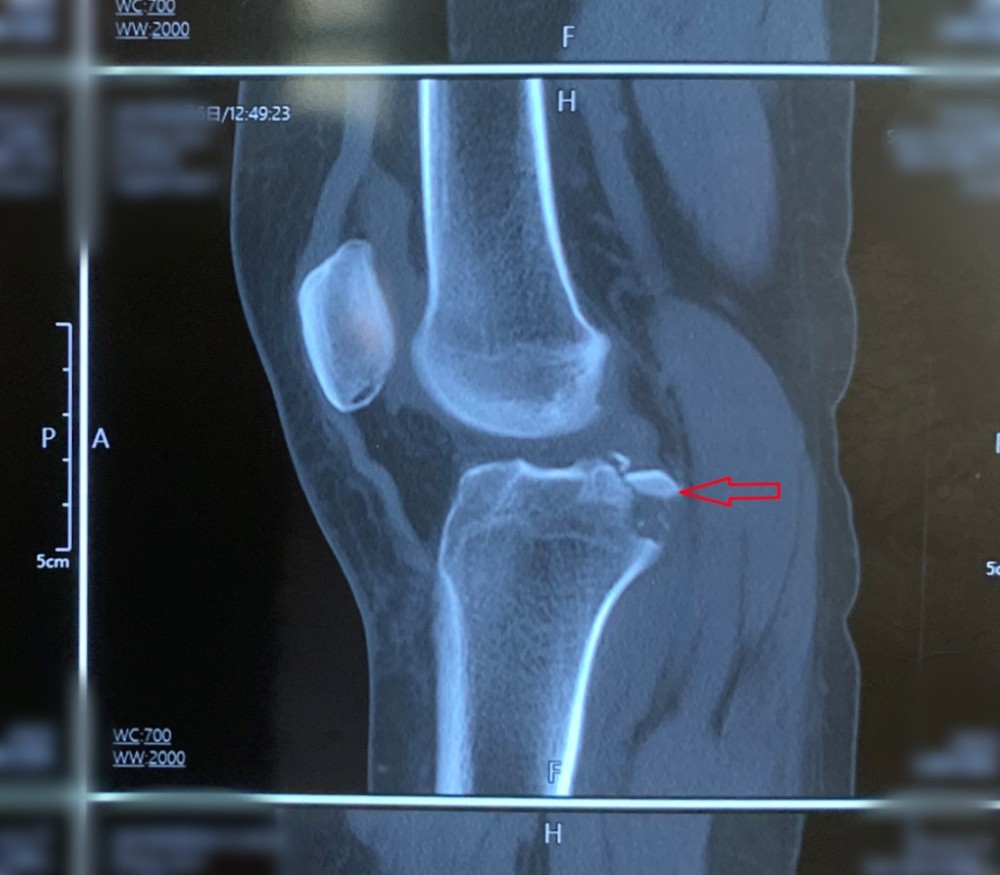

患者因外伤导致左胫骨髁间棘骨折,骨折移位明显,具备手术指征。但患者为年轻女性,担心手术瘢痕影响美观,传统手术方式无法满足患者需求。综合考虑后,91直播 创伤外科中心王建忠教授团队为患者制定了应用骨科手术机器人辅助下进行微创手术的诊疗方案。通过机器人进行数据采集、手术规划等人工智能手段,术中仅用约2cm切口即成功完成手术。与传统手术相比,此类手术切口明显减小,出血量少,达到了微创、精准的手术效果,患者及家属非常满意。

术前CT断层